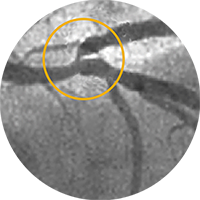

Внутристентовый рестеноз в левой передней нисходящей артерии: ко-регистрация данных с iFR и ВСУЗИ, лазерная атерэктомия, использование баллона с лекарственным покрытием и стентирование.

Хроническая тотальная окклюзия правой коронарной артерии. Изображение предоставил Крейг Томпсон, врач.